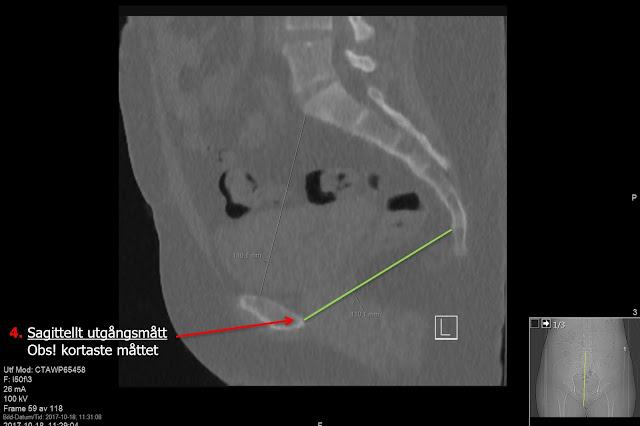

On sagittal reconstruction measure Sagittal Inlet Diameter (Sagittellt ingångsmått) as shortest distance between posterior part of symphysis pubis and promontorium (S1). As well as Sagittal Outlet Diameter (Sagittellt utgångsmått) as shortest distance between posterior part of symphysis pubis and fist mobile joint between sacrum and coccyx.

Sagittal reconstruction for Sagittal Outlet Diameter - measure the shortest between posterior part of symphysis pubis and fist mobile joint between sacrum and coccyx.